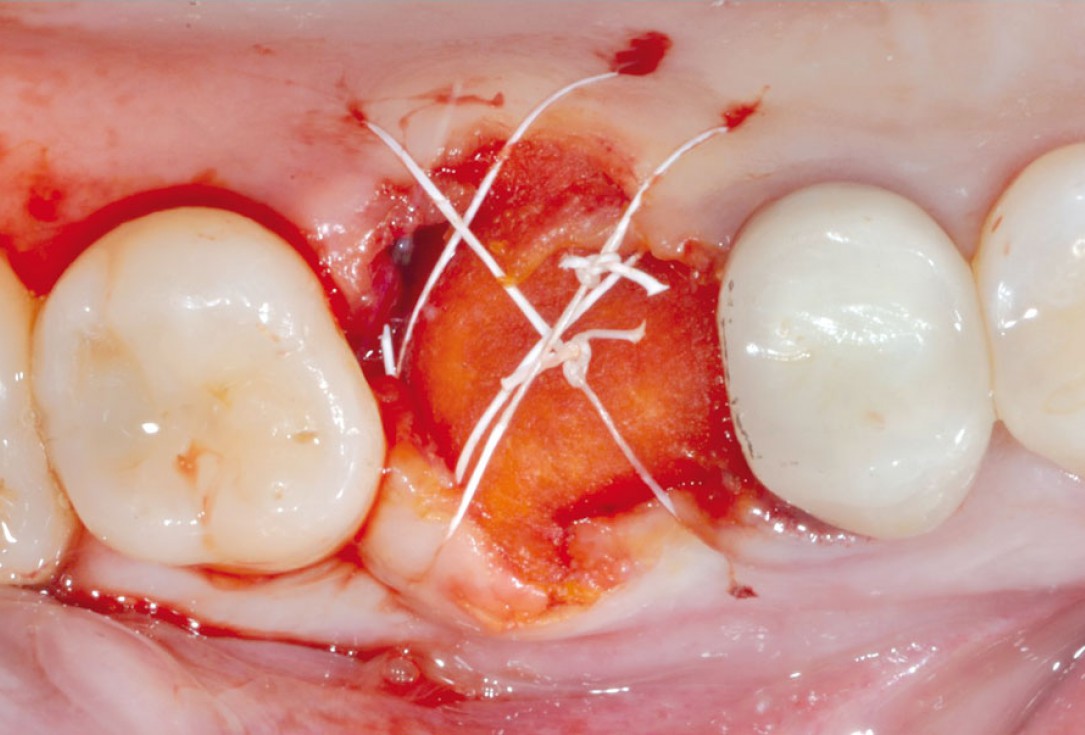

3/11 - Blood clot stabilization with mucoderm®Sealing of a postextraction socket with mucoderm® - Dr. M. Frosecchi